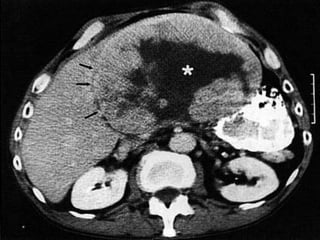

ExamesTGO/TGP, bilirrubinas, GGT, fosfatase alcalina;Alfafetoproteína(70-80%);Desgamacarboxiprotrobina (PIVKA II - 90%);US (Contra: diagnóstico diferencial, metástase e tumor benigno);US com Doppler (avaliar a vascularização);US angiográfica (95% de sensibilidade);TC helicoidal (sensibilidade > 80%);RNM (melhor para detecção de tumores <2cm);Angiografia (pré-operatório);Biópsia (risco de disseminação – 2%).

ExamesTGO/TGP, bilirrubinas, GGT,fosfatase alcalina;Alfafetoproteína(70-80%);Desgamacarboxiprotrobina (PIVKA II - 90%);US (Contra: diagnóstico diferencial, metástase e tumor benigno);US com Doppler (avaliar a vascularização);US angiográfica (95% de sensibilidade);TC helicoidal (sensibilidade > 80%);RNM (melhor para detecção de tumores <2cm);Angiografia (pré-operatório);Biópsia (risco de disseminação – 2%).